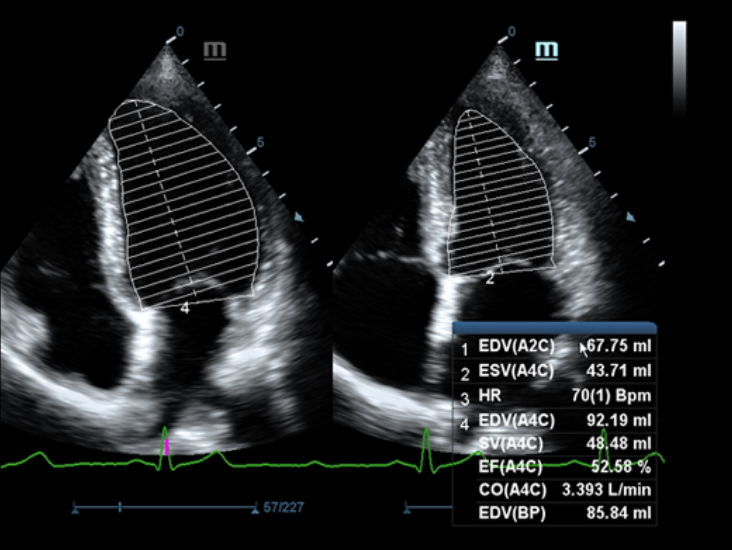

Klinische Bilder